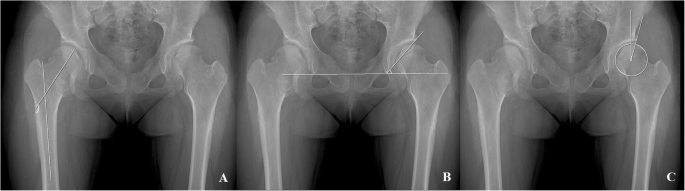

Radiographic analysis was conducted using the last follow-up radiographs in patients who had not undergone any surgical intervention, and the last preoperative radiographs in those who had undergone surgical treatment around the hip joints. For the morphometry of the hip joint in patients with MHE, the femoral neck-shaft angle of Muller [19] was evaluated to assess proximal femur deformity, and Sharp’s acetabular angle [20] and the center-edge (CE) angle [21, 22] were evaluated to assess the deformities of acetabulum (Fig. 2). For FAI evaluation, alpha angle (Fig. 2) of all hips was measured regardless of the presence or absence of symptoms. For IFI evaluation, hip CT studies in patients with MHE were performed in the neutral supine position and the nearest distance between the exostoses and ischium around the lesser trochanter area were measured at axial plane (Fig. 3).

Plain radiographic measurements to evaluate the hip joint deformities. a The femoral neck-shaft angle is determined by measuring the angle created by a line in the central axis of femoral shaft and a second line created by the connection of the femoral head center to the mid portion of the femoral head and neck junction contour. b Sharp’s angle is determined by measuring the angle created by a line connecting the acetabular tear drops and a second line connecting a tear drop and the sourcil end. c The center-edge angle is determined by measuring the angle created by a line connecting the vertical line to the tear drop line through the center of the femoral head and a second line from the center of the hip to the lateral acetabular wall margin